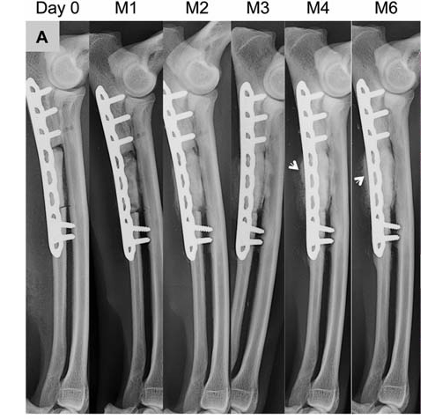

犬尺骨缺损骨修复监测

数据来源:DOI:10.1002/jbm.a.36384

手术后进行X线分析骨缺损位置大小是否合适,植入的材料是否固定良好。后续可定期观察骨缺损修复以及材料融合情况。